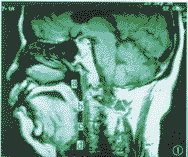

患者,男,60岁。身高1.72m,体重74 kg,主诉夜间睡眠打鼾20年,近2个月夜间憋气。经戴用软垫式口腔矫正器后鼾声基本消失,观察不到夜间睡眠呼吸暂停,无憋气感,日间精神好转。其主要睡眠呼吸功能有所改善:最长睡眠呼吸暂停时间由治疗前的71秒减少到治疗后的21秒;呼吸暂停、低通气指数AHI由治疗前的71次/h减少到治疗后的1.4次/h;最低血氧饱和度由治疗前的75%提高到治疗后的89%。与此同时,上气道主要MRI指标发生了改变:上气道最小截面积由治疗前的42.67 mm2增加到治疗后的55.67 mm2;腭咽平均截面积由治疗前的96.60 mm2增加到143.72 mm2;腭咽体积由治疗前的3 062.25 mm3增加到5 375.91 mm3;舌咽平均截面积由治疗前的103.24 mm2增加到105.47 mm2;舌咽体积由治疗前的4 757.58 mm3改变为3 427.67 mm3;腭咽平均矢状/横向径比由治疗前的0.46增加到治疗后的0.58;舌咽的平均矢状/横向径比由治疗前的0.31增加到0.59(图1~6)。

图1 OSAS患者戴用口腔矫正器治疗前的矢状位MRI影像,a:鼻咽,b腭咽,c舌咽,d喉咽

图2 治疗后的矢状位 MRI影像,图示同图1